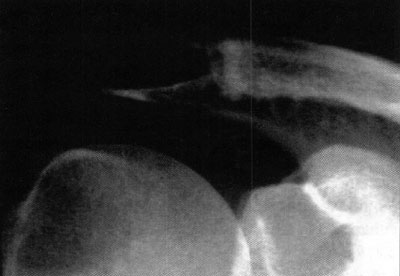

Foto 8: Radiografía preoperatoria. Artrosis con pinzamien-

Foto 9: Radiografía postoperatoria. Margen de resección satisfactorio (11 mm).